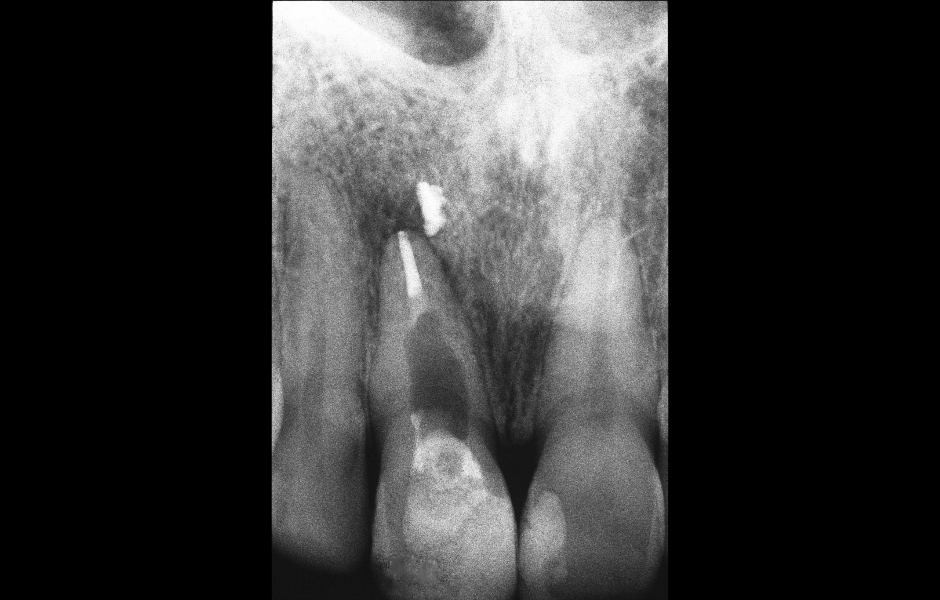

Obr. 1.1: Předoperační rentgenový snímek horního pravého středního řezáku.

Termín chirurgická endodoncie označuje obor stomatologie, který se zabývá diagnostikou a léčbou lézí endodontického původu, jež nedostatečně reagují na konvenční endodontické ošetření nebo je nelze konvenční cestou ošetřit vůbec.¹ Cílem chirurgické endodoncie je dosažení trojrozměrného vyčištění, opracování a zaplnění apikální části kořenového kanálkového systému, která není přístupná běžným ortográdním přístupem dřeňovou dutinou, ale pouze po odklopení chirurgického laloku (obr. 1.1).